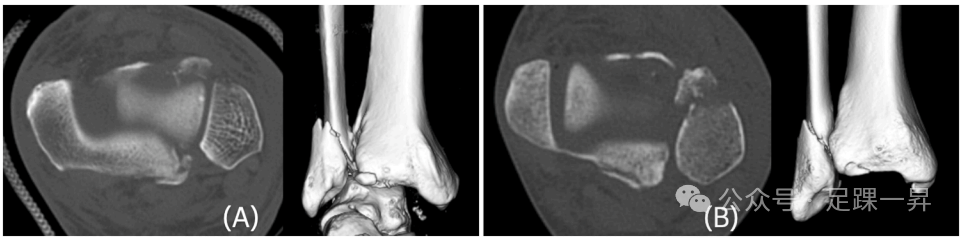

图片

图示侧向移位(LD)型后踝骨折块。后踝骨折块向外侧移位,骨折块内侧存在间隙。图示病例为Mason和Molloy 2A型。